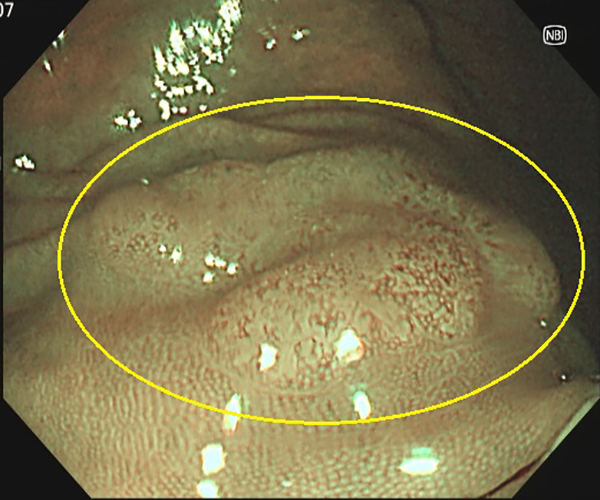

⑤大腸がん(側方発育型腫瘍(LST))

1. 大腸ポリープ既往歴があり、定期的検査として内視鏡検査を施行、横行結腸に10mm強の表面比較的平滑な扁平隆起を認めます。

2. NBI画像処理で表面構造の異常(周辺が均一な小円形構造に対し、不均一)を認めます。側方発育型腫瘍(非顆粒型)であり内視鏡的粘膜切除術で治癒、粘膜内癌と診断されました。